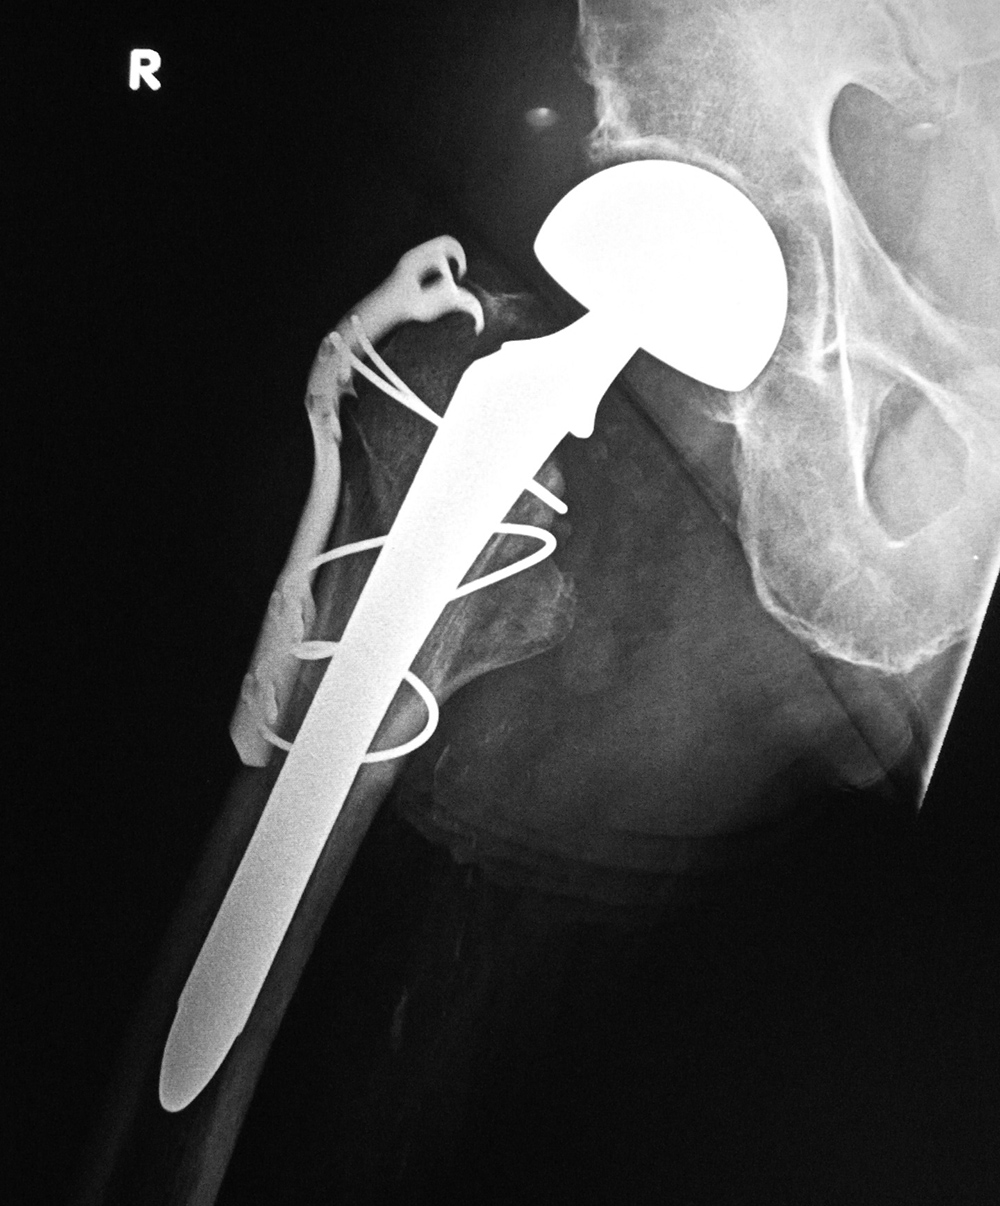

| Bipolar hemiarthroplasty with claw plate and cables

| 78 year-old woman with prior bipolar hemiarthroplasty; presently treated with claw plate and cables for intertrochanteric fracture.

|